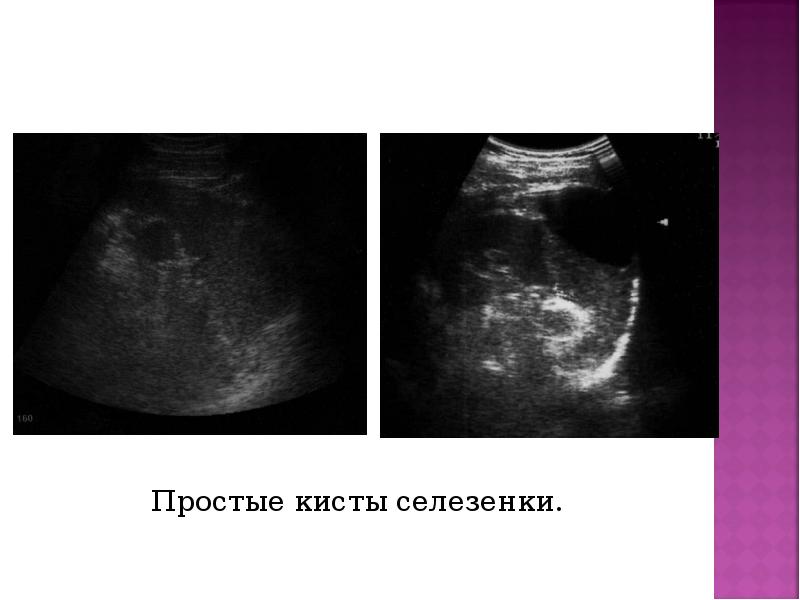

- 34. Простые кисты селезенки. Простые кисты селезенки.

- 33. Первичные врожденные кисты имеют эпителиальную или эндотелиальную выстилку Первичные врожденные кисты